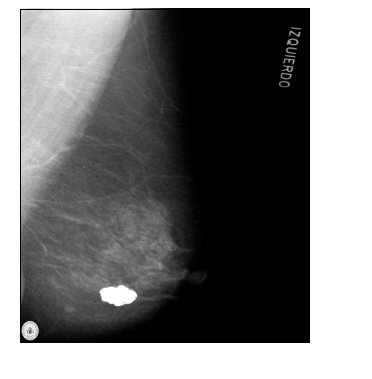

Paciente de 64 anos, menopausa aos 54 anos, nuligesta, é atendida no ambulatório de ginecologia com a mamografia abaixo. Refere prima materna com história de câncer de mama. Ao exame físico, apresenta mamas pendulares, sem abaulamentos ou retrações, sem nódulos palpáveis, axilas livres e descarga papilar negativa. A conduta proposta para essa paciente é realizar: